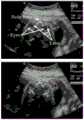

图4是产前超声视频图像标注示意图;Fig. 4 is a schematic diagram of prenatal ultrasound video image annotation;

图4为产前超声视频图像标注示意图,部分显示了胎儿心脏四腔标准切面分类预测任务的一个视频标注示例,该视频共包含49帧,图中选取显示了其中的8帧超声图像,其中最右边的数字0代表非标准切面,1代表标准切面,虚线代表标准切面,实线代表非标准切面,从图中可以看到标签是不连续的,即标准切面出现的片段很短,在某些情况下,两个标准切面之间也可能出现非标准切面,这主要是因为探头移动、背景噪音以及器官运动的原因,因此视频分析中常用的基于片段候选的预测算法并不适用于标准切面预测任务,本实施例提供一种针对帧级任务的方法来实时生成细粒度和密集的时序分类预测结果。Figure 4 is a schematic diagram of prenatal ultrasound video image labeling, which partially shows an example of video labeling for the four-chamber standard view of the fetal heart. The